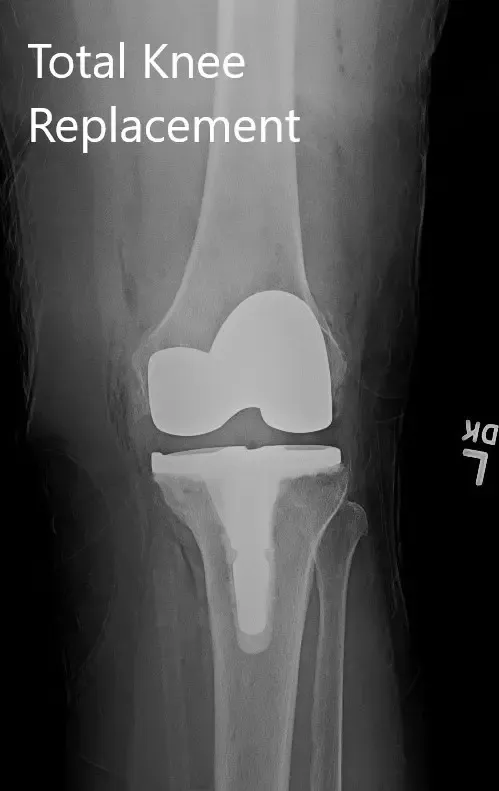

OPERACIÓN: Artroplastia total de rodilla izquierda.

IMPLANTES UTILIZADOS: rótula totalmente poli de 52 mm con fémur tamaño 6 y tibia tallada tamaño E con extensión de tallo de 14 mm.

Radiografía postoperatoria que muestra la articulación de la rodilla izquierda con prótesis en vistas anteroposterior y lateral